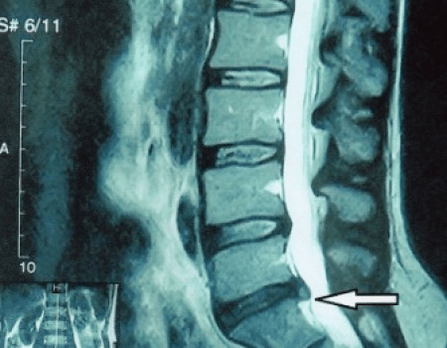

Zënter datt d'Discs selwer nëmme mat CT oder MRI gesi kënne ginn, ginn d'Magnéitesch Resonanz an d'Röntgen-Computertomographie uginn fir d'intern Struktur vum Knorpel a Formatiounen wéi Protrusiounen an Hernias ze klären. Also, mat der Hëllef vun dëse Methoden, gëtt eng Diagnostik präzis gemaach, an d'Resultat vun der Tomographie ass eng Indikatioun, a souguer en aktuellen Guide, fir d'chirurgesch Behandlung vun enger Hernia an der Neurochirurgie.

- Wann Dir eng Hernia hutt, da musst Dir dynamesch iwwerwaachen, reegelméisseg MRI maachen, vermeiden hir Gréisst ze vergréisseren oder modern minimal invasiv chirurgesch Behandlung ausféieren, well ouni Ausnam all konservativ Methode fir d'Vergréisserung vun der Osteochondrose ze behandelen, verloossen d'Hernia op der Plaz, an eliminéieren nëmmen temporär Symptomer: Entzündung, Péng, Schéissen a Muskelschmerzen.